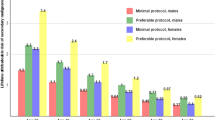

Lifetime attributable risk (LAR) and relative risk for radiation-induced leukemia, liver, and stomach cancer

For leukemia, LAR ranged from five excess cases per 100,000 patients in 60-year-old women undergoing a simple procedure in the decubitus position, to 58 excess cases in 30-, 40-, and 50-year-old men undergoing the procedure in the prone position with the CT gantry in a tilted position. For liver cancer, LAR ranged from one excess case in 60-year-old women undergoing a simple procedure in the prone position with a tilted gantry, to 21 excess cases in 30-year-old men undergoing a complex procedure in the decubitus position. For stomach cancer, LAR ranged from three excess cases in 60-year-old men undergoing the procedure in the lateral decubitus position, to 28 excess cases in 30-year-old women undergoing the procedure in the prone position (Table 4).

The highest relative risk of 1.074 was seen for the incidence of leukemia in 30-year-old women undergoing the procedure in the prone position with a gantry tilted (Table 5). The associated estimated LAR for women at this age was 43 excess cases per 100,000 patients (Table 4).

For more complex cryoablation procedures, the longer CT fluoroscopy time resulted in a greater estimated lifetime attributable and relative risk of developing radiation-induced cancer in radiosensitive organs. We estimate that the lifetime excess risk of developing leukemia using the tilted gantry technique is significantly higher than the excess risk of cancer induction for other techniques and types of cancer. The excess risk of leukemia using a tilted gantry is two times higher than the neutral gantry position for any patient age, gender, and level of procedural complexity. Younger women who undergo complex procedures have a higher risk. After a single complex procedure using a tilted gantry, the estimated lifetime excess relative risk was 6.7 and 7.4 % in 60-year-old and 30-year-old females, respectively. We suspect that the combination of a tilted gantry and prone patient position may expose the medullary hematopoietic tissue of the lumbar spine to more incident radiation compared to the neutral gantry position. For comparison, the lifetime excess relative risk for breast or lung cancer in young women aged 15–25 years undergoing a single CT angiographic examination of the heart is 5.5 %, which is a high excessive risk in this susceptible population [13]. The mechanism of the tilted gantry technique’s potential of inducing leukemia should be investigated further, perhaps in a small animal model.

Our estimates of lifetime excess relative risk of cancer for solid tumors of the stomach and liver, while the patient is in the prone or lateral decubitus position and with the tilted CT gantry range from 1.0 to 2.0 % for simple and intermediate complexity procedures. Although the radiation-related risk is small, the use of this technology to treat renal tumors, along with the other inherent risks of this procedure, should be weighed against the risks posed by alternative procedures (e.g., general anesthesia and surgical tumor resection).

As expected, the lifetime excess relative risk during more technically complex procedures is higher. This is especially true in younger women, for whom the lifetime excess risk for stomach cancer in a 30-year-old woman is as high as 3.9 % for a single complex cryoablation procedure. The potential for cancer induction in younger patients is more substantial, especially young patients with hereditary conditions such as Von Hippel-Lindau syndrome, who may have multiple solid renal tumors and could undergo numerous complex cryoablation procedures. Over time, the cumulative radiation dose from diagnostic CT examinations also must be considered in this patient population. For all age groups, the risk of radiation-induced cancer would be expected to increase if multiple follow-up multi-detector CT studies were performed. Although this cumulative effect has been established to increase breast cancer risk [14], it likely applies to the radiation-induced malignancies examined in this study as well.